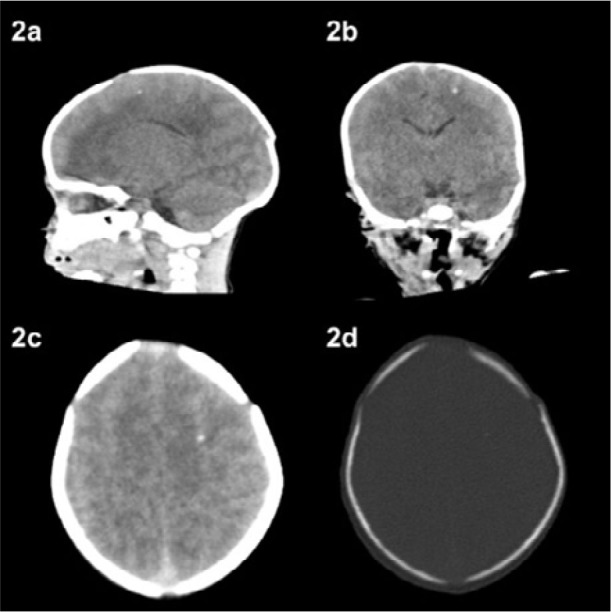

Case description: The mothers had a previous serological diagnosis of toxoplasmosis conducted during prenatal care, with non-reactive (<10 IU/mL) IgM and reactive IgG (>10 IU/mL), and were considered "immune" to the infection. Both infants were born with sequelae of the congenital infection, including neurological and ocular alterations.

Comments: Managing gestational toxoplasmosis in susceptible pregnant women is a considerable challenge in several countries, especially in South America. It is necessary to diagnose and monitor chronic gestational toxoplasmosis, as it may result from reactivation or reinfection. Both forms can cause sequelae and irreparable damage to newborns. In addition, it is essential to guide all pregnant women on how to avoid contact with Toxoplasma gondii, regardless of their serological status.